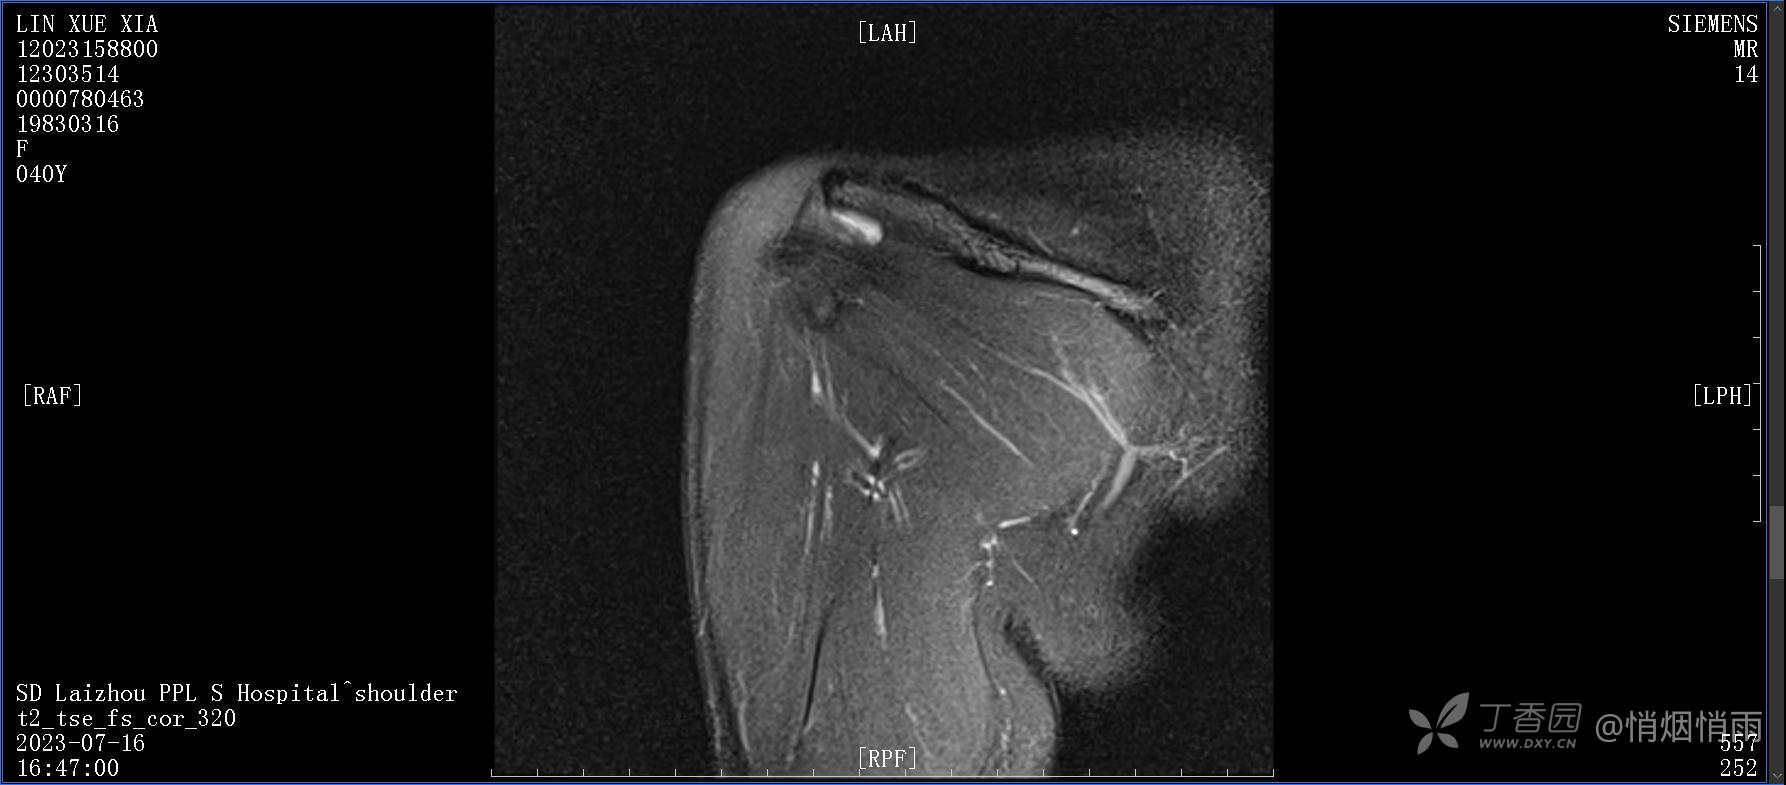

查体:右肩关节局部轻度肿胀,肩胛区压痛明显,痛处不固定,肩关节痛性活动受限,jobe test(+),lift -off test(+),中指、环指感觉较余指减退,余肢端感觉及血运情况可。

目前的诊断,暂时依据辅助检查诊为肩袖损伤,但是患者疼痛的性质和特点,却不是单纯的肩袖损伤所致。考虑过胸廓出口综合征,但是该疾病会出现肩胛区的疼痛吗?(由于考虑到费用的问题,没再进行下一步的检查)带状疱疹会有如此的症状吗?